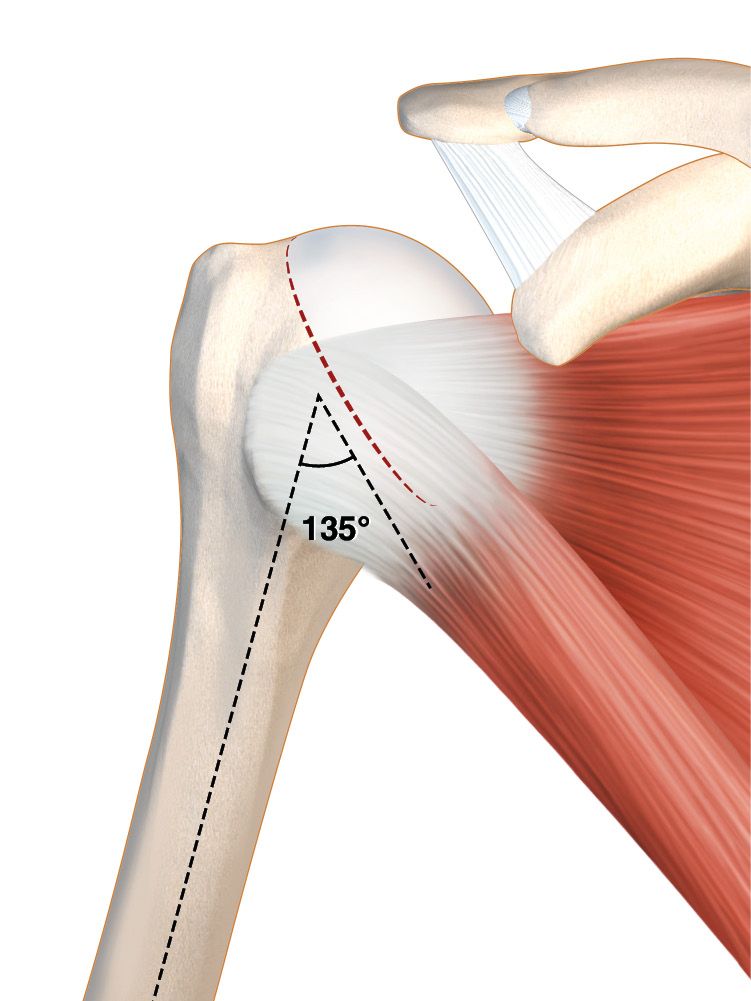

For all patients the Lima SMR implant had been used. This implant has a glenosphere (40mm or 44mm diameter) which comprises two-thirds of a non-eccentric polyethylene sphere. The humeral cut is made at 135° using a guide, and the metaphyseal insert (three thicknesses) is at an angle of 7°, which puts the CCD angle of the RTSA at 142°. We make our cuts with 20° retroversion.

4. Humeral cut

a. The cut must be sufficient to properly expose the glenoid without tension whilst at the same time sparing the metaphyseal bone.

b. The upper insertion of the subscapularis tendon can be used to guide the height of the cut. The cut certainly shouldn't go beyond this point and can even be smaller to preserve a little more of the bone (Fig. 10).

c. Using an intramedullary guide is advisable when first starting out, for ‘large’ shoulders and for difficult exposures. It has the advantage of ensuring the correct angle and retroversion (Fig. 11)

d. Retroversion is typically 20°, but depending on the surgeon’s preferences it can be adapted to the patient anatomy and retroversion. It is important to visualize the insertion of the infraspinatus tendon and cut close to the anatomic neck.